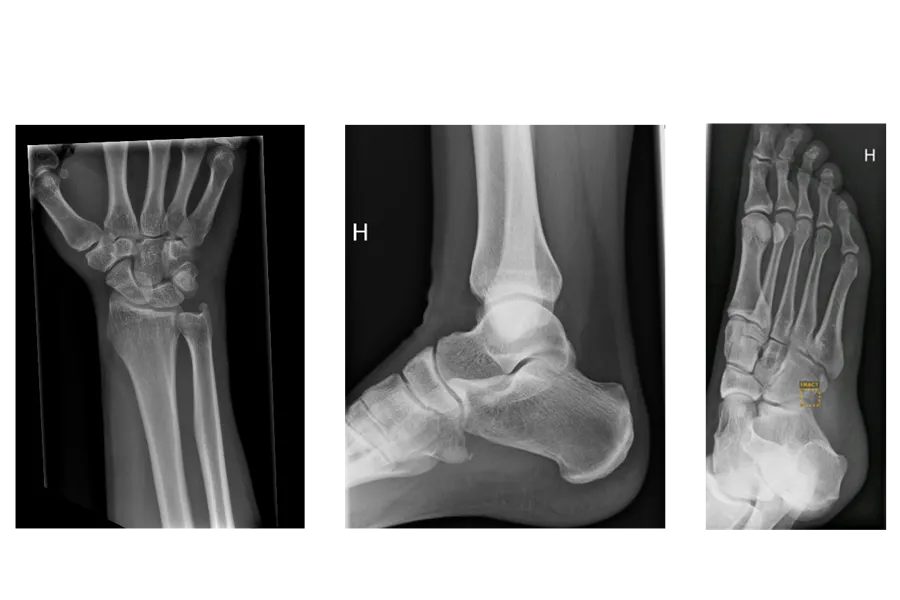

- I Vestre Viken har man begynt å ta i bruk KI i stor skala, og i november besøkte jeg Drammen sykehus hvor man blant annet benytter KI i tolkningen av røntgenbilder. Erfaringene så langt er gode, sa Kjerkol.

Hun la til at det fra slutten av august til tidlig november ble, bare ved Bærum sykehus, spart over 300 legekonsultasjoner.